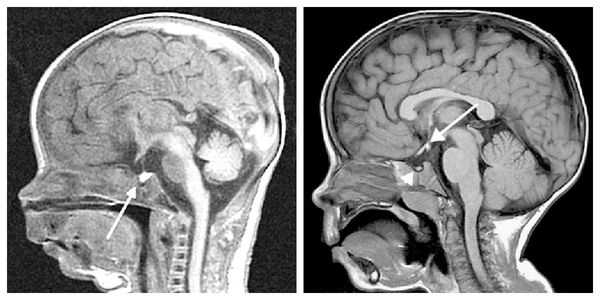

При необходимости проводится МРТ головного мозга и гипофиза с контрастированием [6] . Она позволяет исключить или подтвердить наличие объёмных образований области гипофиза и головного мозга.

Нейровизуализацию опухоли гипофиза позволяет осуществить рентгенография черепа и зоны турецкого седла, МРТ и КТ головного мозга. Рентгенологически могут определяться увеличение размеров турецкого седла и эрозия его дна, а также увеличение нижней челюсти и пазух носа, утолщение костей черепа, и расширение межзубных промежутков. С помощью МРТ головного мозга возможно увидеть опухоли гипофиза диаметром менее 5 мм. Компьютерная томография подтверждает наличие аденомы и ее точные размеры.

У некоторых пациентов с мутацией конкретных генов выявляется гиперплазия передней доли гипофиза (аденогипофиза). В процессе жизни может произойти её атрофия вплоть до формирования синдрома "пустого турецкого седла" — недостаточности области головного мозга, где расположен гипофиз. Данный синдром приводит к внедрению мягкой мозговой оболочки в полость турецкого седла, сдавлению и уменьшению гипофиза, что нарушает или полностью прекращает его работу.